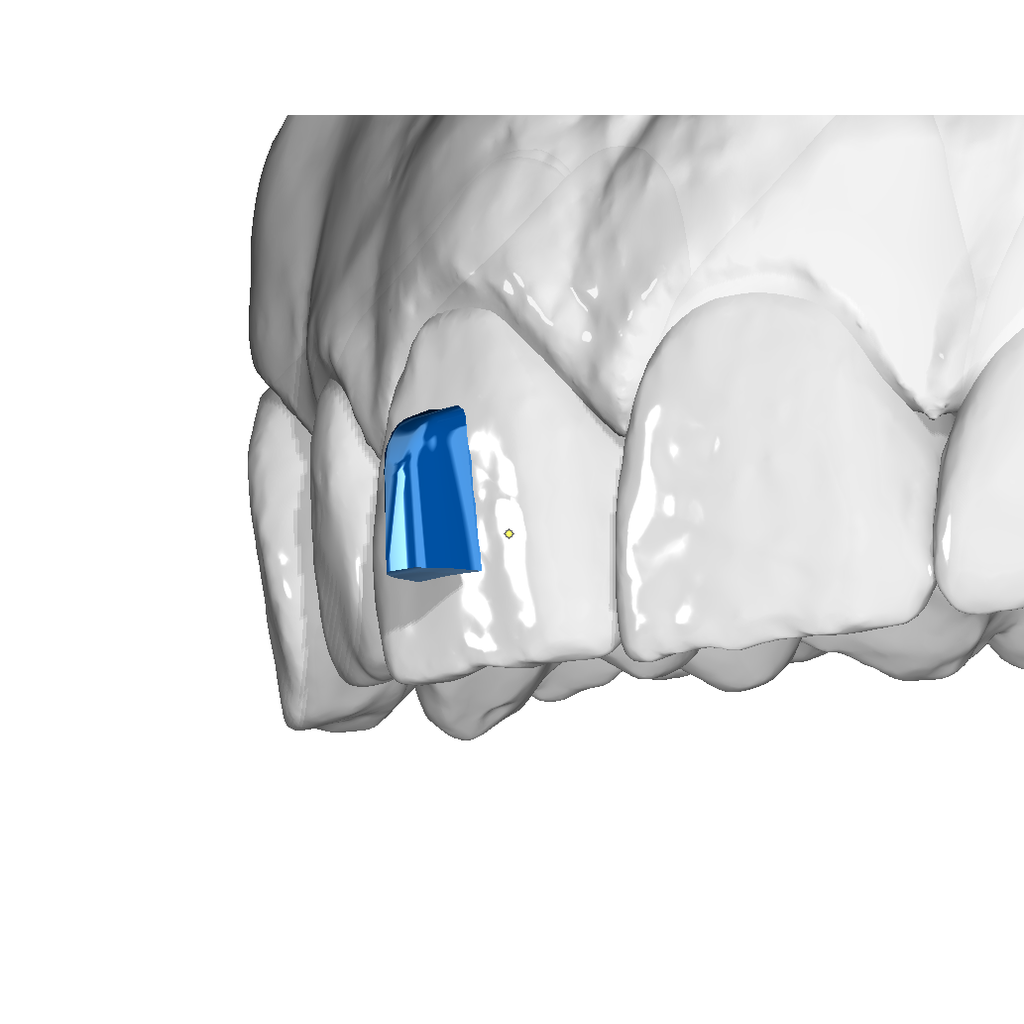

Vertical Attachment Template for Aligner Therapy

The vertical attachment is the workhorse of aligner biomechanics. Its vertical orientation provides the leverage needed for derotation, full bodily movement, and demanding distalization sequences — making it an essential part of any comprehensive aligner case.

✔ Derotation & bodily movement — vertical geometry delivers the control needed for complex 3D tooth movements

✔ Semi-sequential distalization — reliable anchorage for staged posterior movement

✔ Four size options — from 3×2 mm to 6×3.5 mm to match any tooth and indication

✔ Digital O3P template — ready to place directly in OnyxCeph